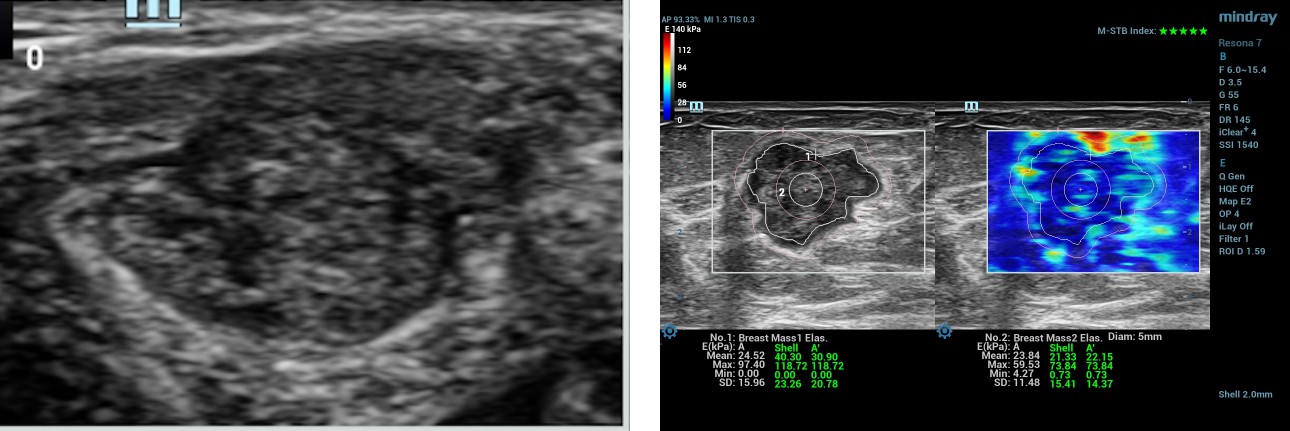

Case Report 1

57-year-old female, patient A presented with a left breast lump of 6 months duration. There was a lump measuring 19x15mm in size at the 2 OŌĆÖclock position of the left breast. B-mode ultrasound categorized this lesion as BIRADS 5. Before performing the biopsy, the patient underwent shear wave elastography (SWE) using L14-3WU (bandwidth frequency = 3.8-15.4 MHz, FOV-50.8mm) linear array transducer of Resona 7 diagnostic ultrasound system by Mindray Medical International, Shenzhen, China.

- The ratio of the lesion to normal breast tissue SWE values

The Maximum and mean values in the selected ROI manually along the edge of the lesion are 97.4 kPa and 24.5 kPa. The maximum value in the 2mm shell around the lesion is 118.7 kPa. The maximum and mean values in the lesion + shell are 118.7 kPa and 30.9kPa. Maximum and minimum values in the center of the lesion with a circular ROI measuring 5mm in diameter are 59.5kPa and 23.8kPa.